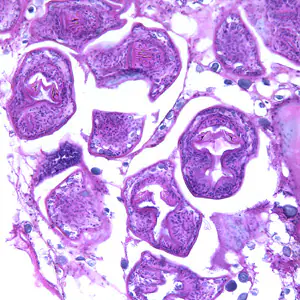

Echinococcus granulosus in tissue.

Upon ingestion of eggs by the human host, the oncospheres migrate from the intestinal lumen to other body sites via circulation and develop into hydatid cysts. These cysts can be found in any part of the body, but are most common in the liver, lung and central nervous system.